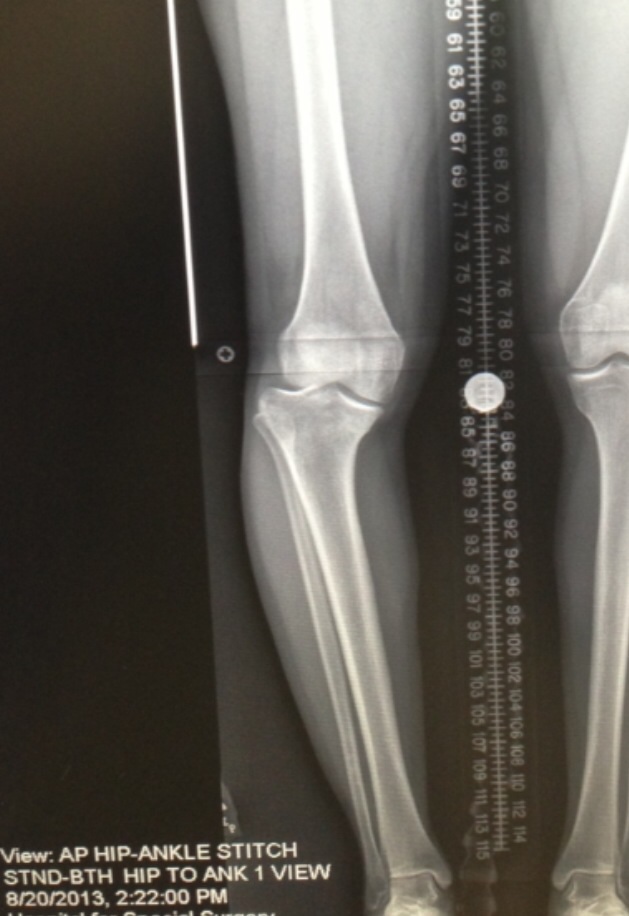

From birth I had a noticeable bow in my right leg, which was difficult growing up because other kids made fun of me. I learned to accept the way my leg looked because I didn't think there was anything I could do to fix it and my condition didn't pose a serious health risk or prevent me from being active at the time. In my late 20's my interest in fitness peaked and I decided that I wanted to be a personal trainer. I started working out in the gym and one day while on the treadmill, I noticed an unusual feeling in my right knee. I didn't think much about it initially but then it began to swell and feel uncomfortable. After seeking medical advice it was discovered that I had a torn meniscus. Upon further examination, they also found that there was a profound misalignment in my right knee that required attention. They informed me that if I allowed it to stay that way, over time it would lead to major mobility concerns.

I sought the advice of a number of doctors and was dismayed when the possibility of a complete knee replacement was brought up; which at my age was something I perceived as not ideal since I was relatively young. After speaking with Dr. Rozbruch, who came highly recommended for this type of leg issue, he gave me hope. He knew exactly what needed to be done to correct the alignment while keeping my knee intact. The surgery was successful. Dr. Rozbruch was extremely professional, confident, and competent. He has changed my life and allowed me to be able to walk, run, and dance circles around the gym. I am thankful to Hospital for Special Surgery and their dedicated staff for being very accommodating and helpful while I stayed there for my 3 knee surgeries this year.